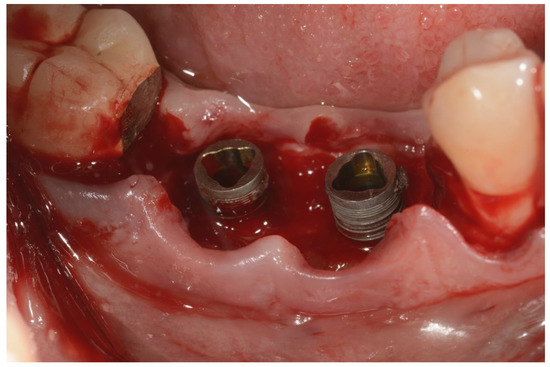

2. Materials and Methods